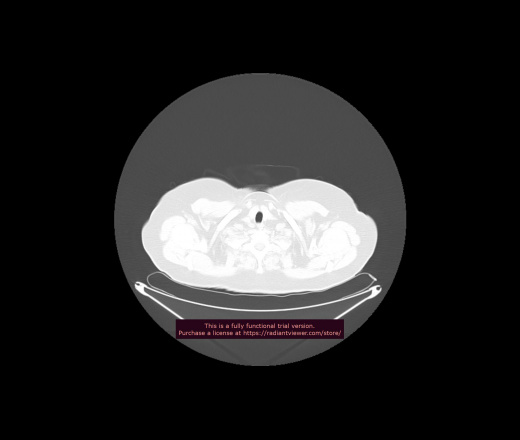

Уважаемые коллеги, если имеется интерес, сможете ли Вы спрогнозировать дальнейшее +-одинаковое течение процесса у 4 данных разных пациентов? Зацепиться где-то можно очень просто, где-то нельзя.